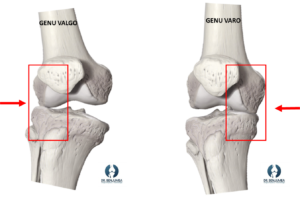

Cuando padecemos de genu varo, la mitad interna de la rodilla trabajará con una carga mayor de lo que le corresponde, y con el genu valgo será la mitad externa. Esto significa que día a día durante toda la vida, una zona de la rodilla está trabajando más de lo que le corresponde, lo que puede llevar a una sobrecarga de esta zona. Con el tiempo, puede aparecer dolor por sobrecarga, típicamente cuando realizamos impacto sobre la rodilla (andar, correr, etc).

El problema más importante surge cuando el cartílago articular de esa zona de la rodilla se desgasta por ese sobreuso. Un desgaste acelerado del cartílago inicial provocará un aumento aun mayor de la carga en ese compartimento, estableciendose un circulo vicioso donde ese desgaste avanza con el tiempo y finalmente se establezca una artrosis de rodilla. Junto al cartílago, también pueden aparecer lesiones en los meniscos por sobrecarga.